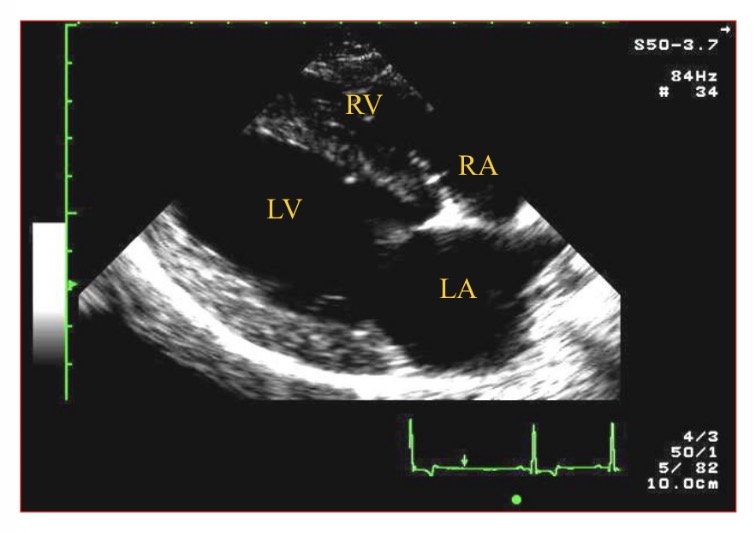

R para sternal long axis 4 chamber view

Types of views - RPS view which chamber is clostest to probe

RV

Which chamber is A

LV

Which chamber is B

LA